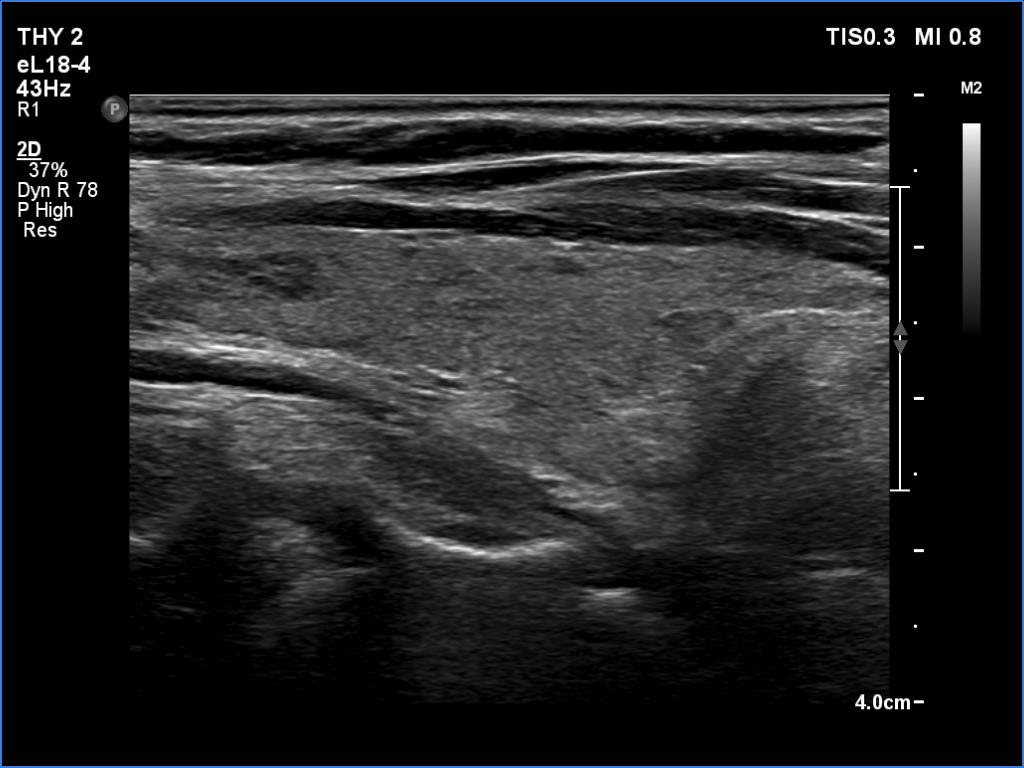

Ultrasonography. The thyroid was echonormal. There were several hypoechoic areas in the right lobe. The left lobe had a large minimally hypoechoic nodule with several tiny cystic areas. The lesion had numerous back wall figures.

In the first part of the ultrasound examination, when the transducer was continuously moving over the thyroid gland, it was not detectable that the contents of the nodule were showing flow. When we stopped the transducer, it became clear that the seemingly solid mass was actually a dense liquid in a continuous flow. On Doppler examination, 'circulation' was visible in continuously changing places.

If it had really been about blood vessels, according to the cycle of circulation,

it would have disappeared once, at other times the flow would have reappeared, but at the same time we would have always seen it in the same place.